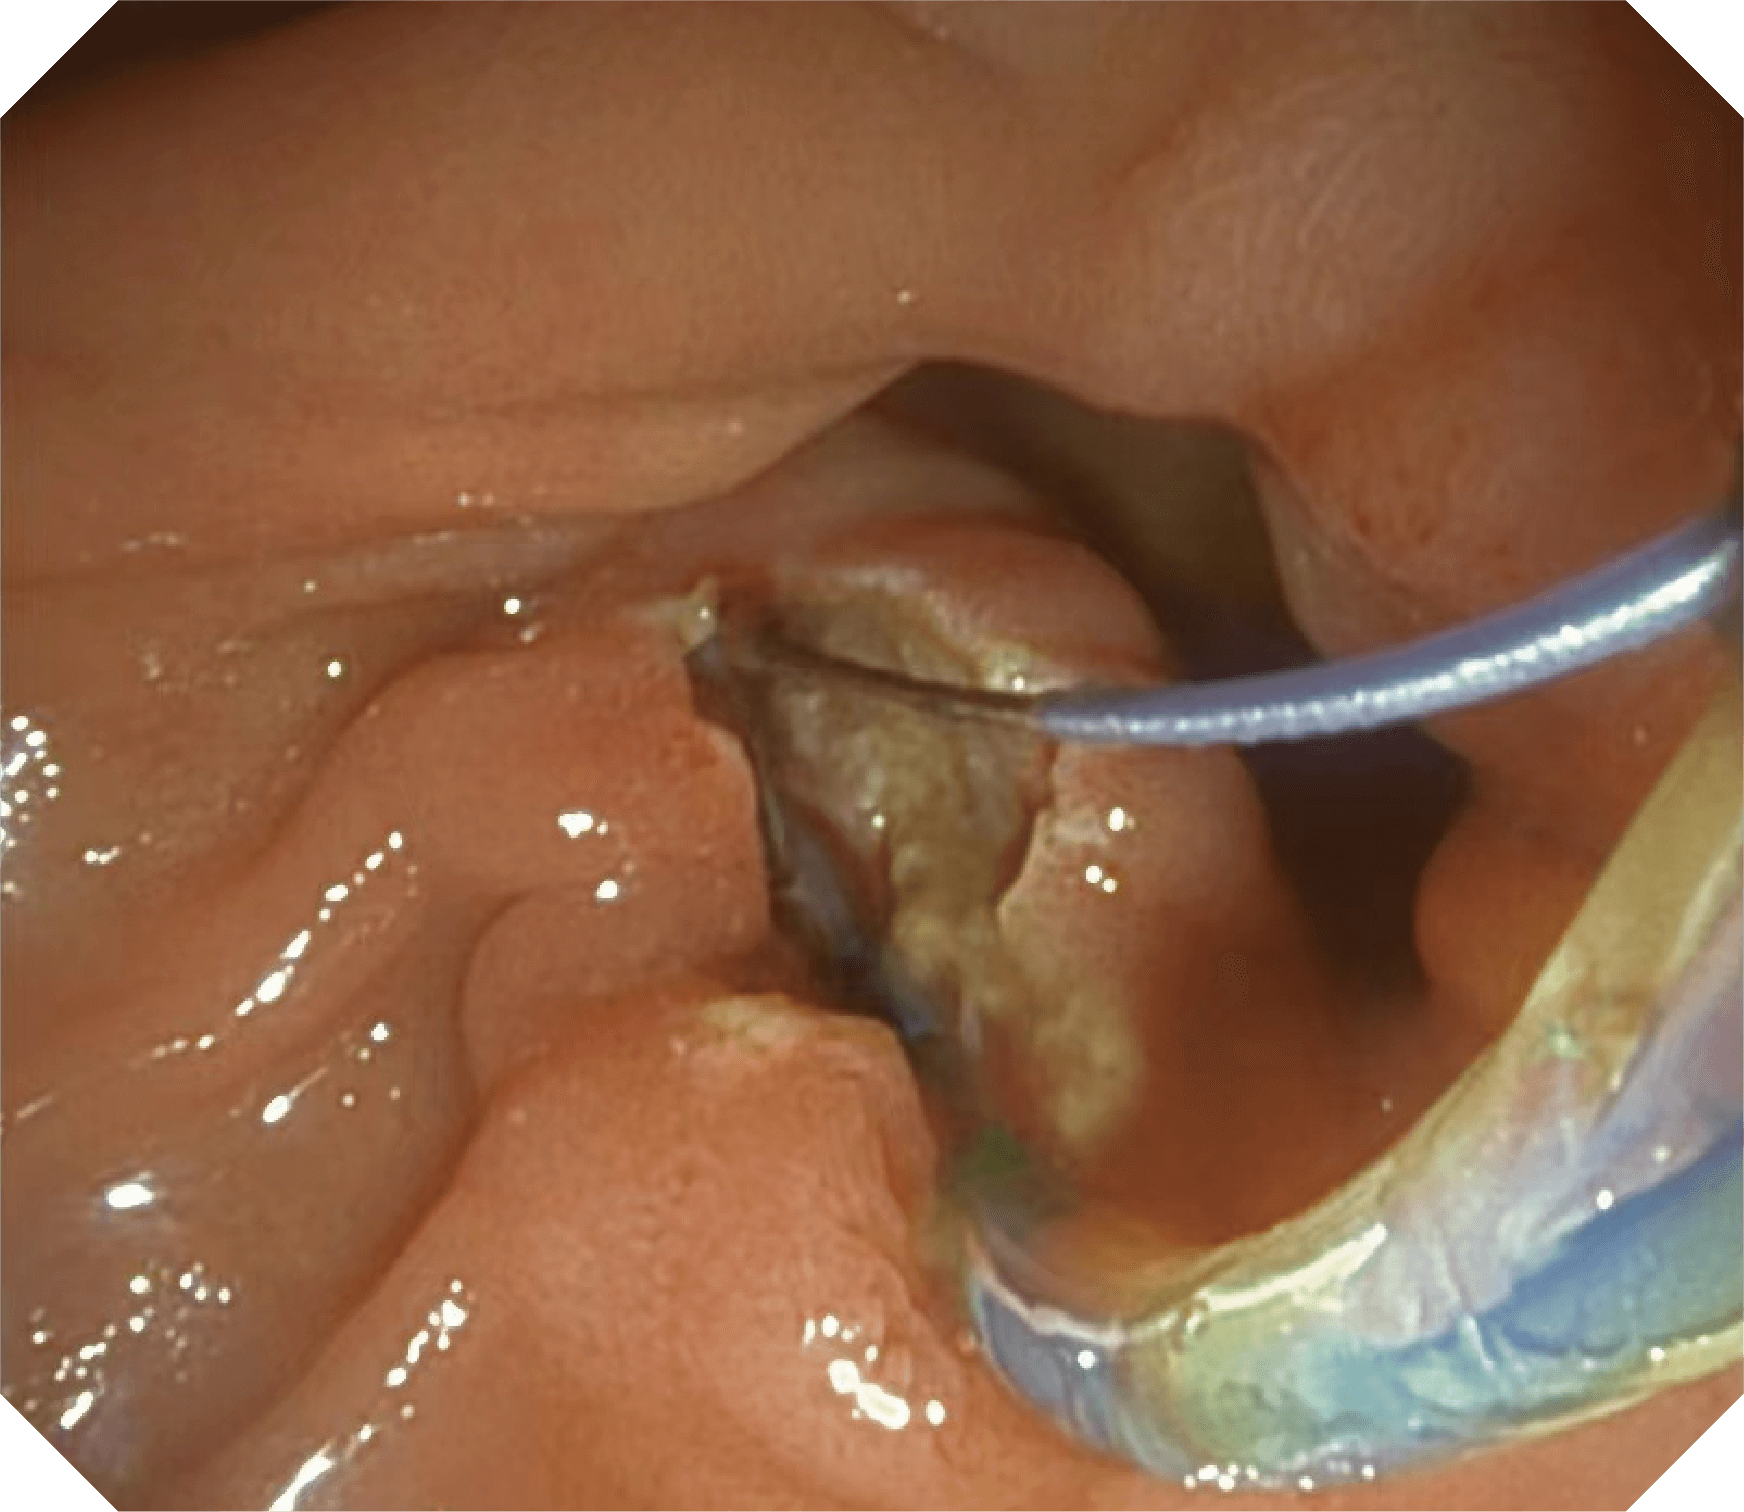

导丝机械锁紧功能

V槽设计提升导丝控制

优异的手术器械抬举性

更好的通过性,更稳定的镜体支撑力

当切开刀伸出视野外时,导向面引导其回归视野